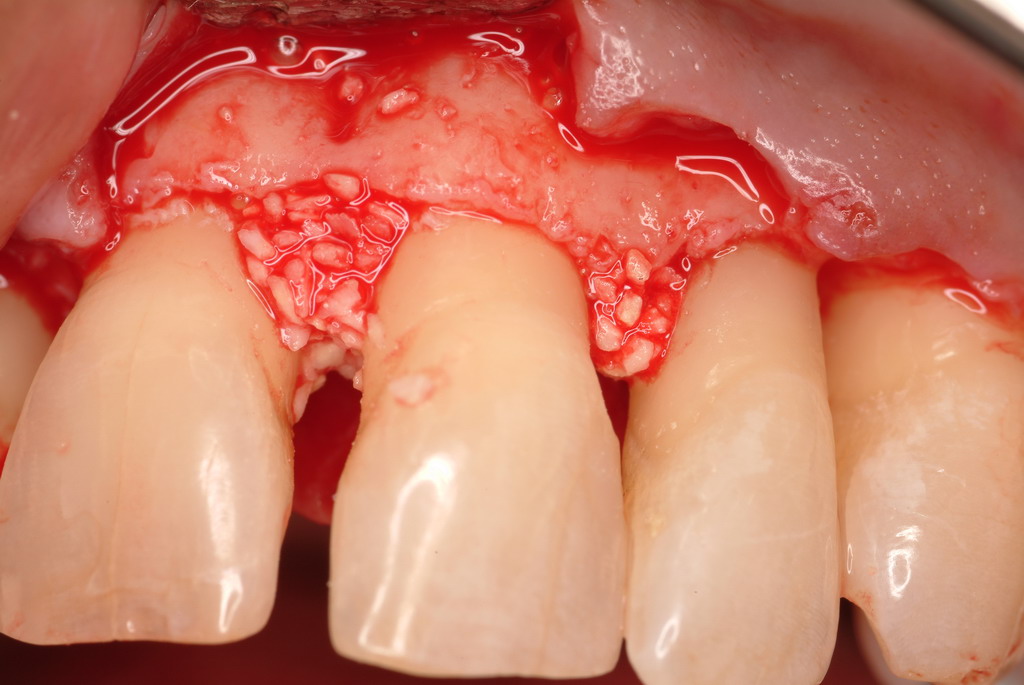

The defect was obturated with mineralized freeze-dried bone and hydrated with platelet-derived growth factor. As with any growth factor, when implementing it clinically, all growth factors require a carrier to bring that growth factor to the desired site, which do not elicit an inflammatory response. In this situation, it is the mineralized freeze-dried bone allograft. This combination was demonstrated by Rosen et al8 to be efficacious in treating intrabony defects. A biologic approach was taken both in terms of the graft and membrane (Figure 19). Primary closure was achieved.

An amnion-chorion membrane adapted over the bone graft.

Figure 19